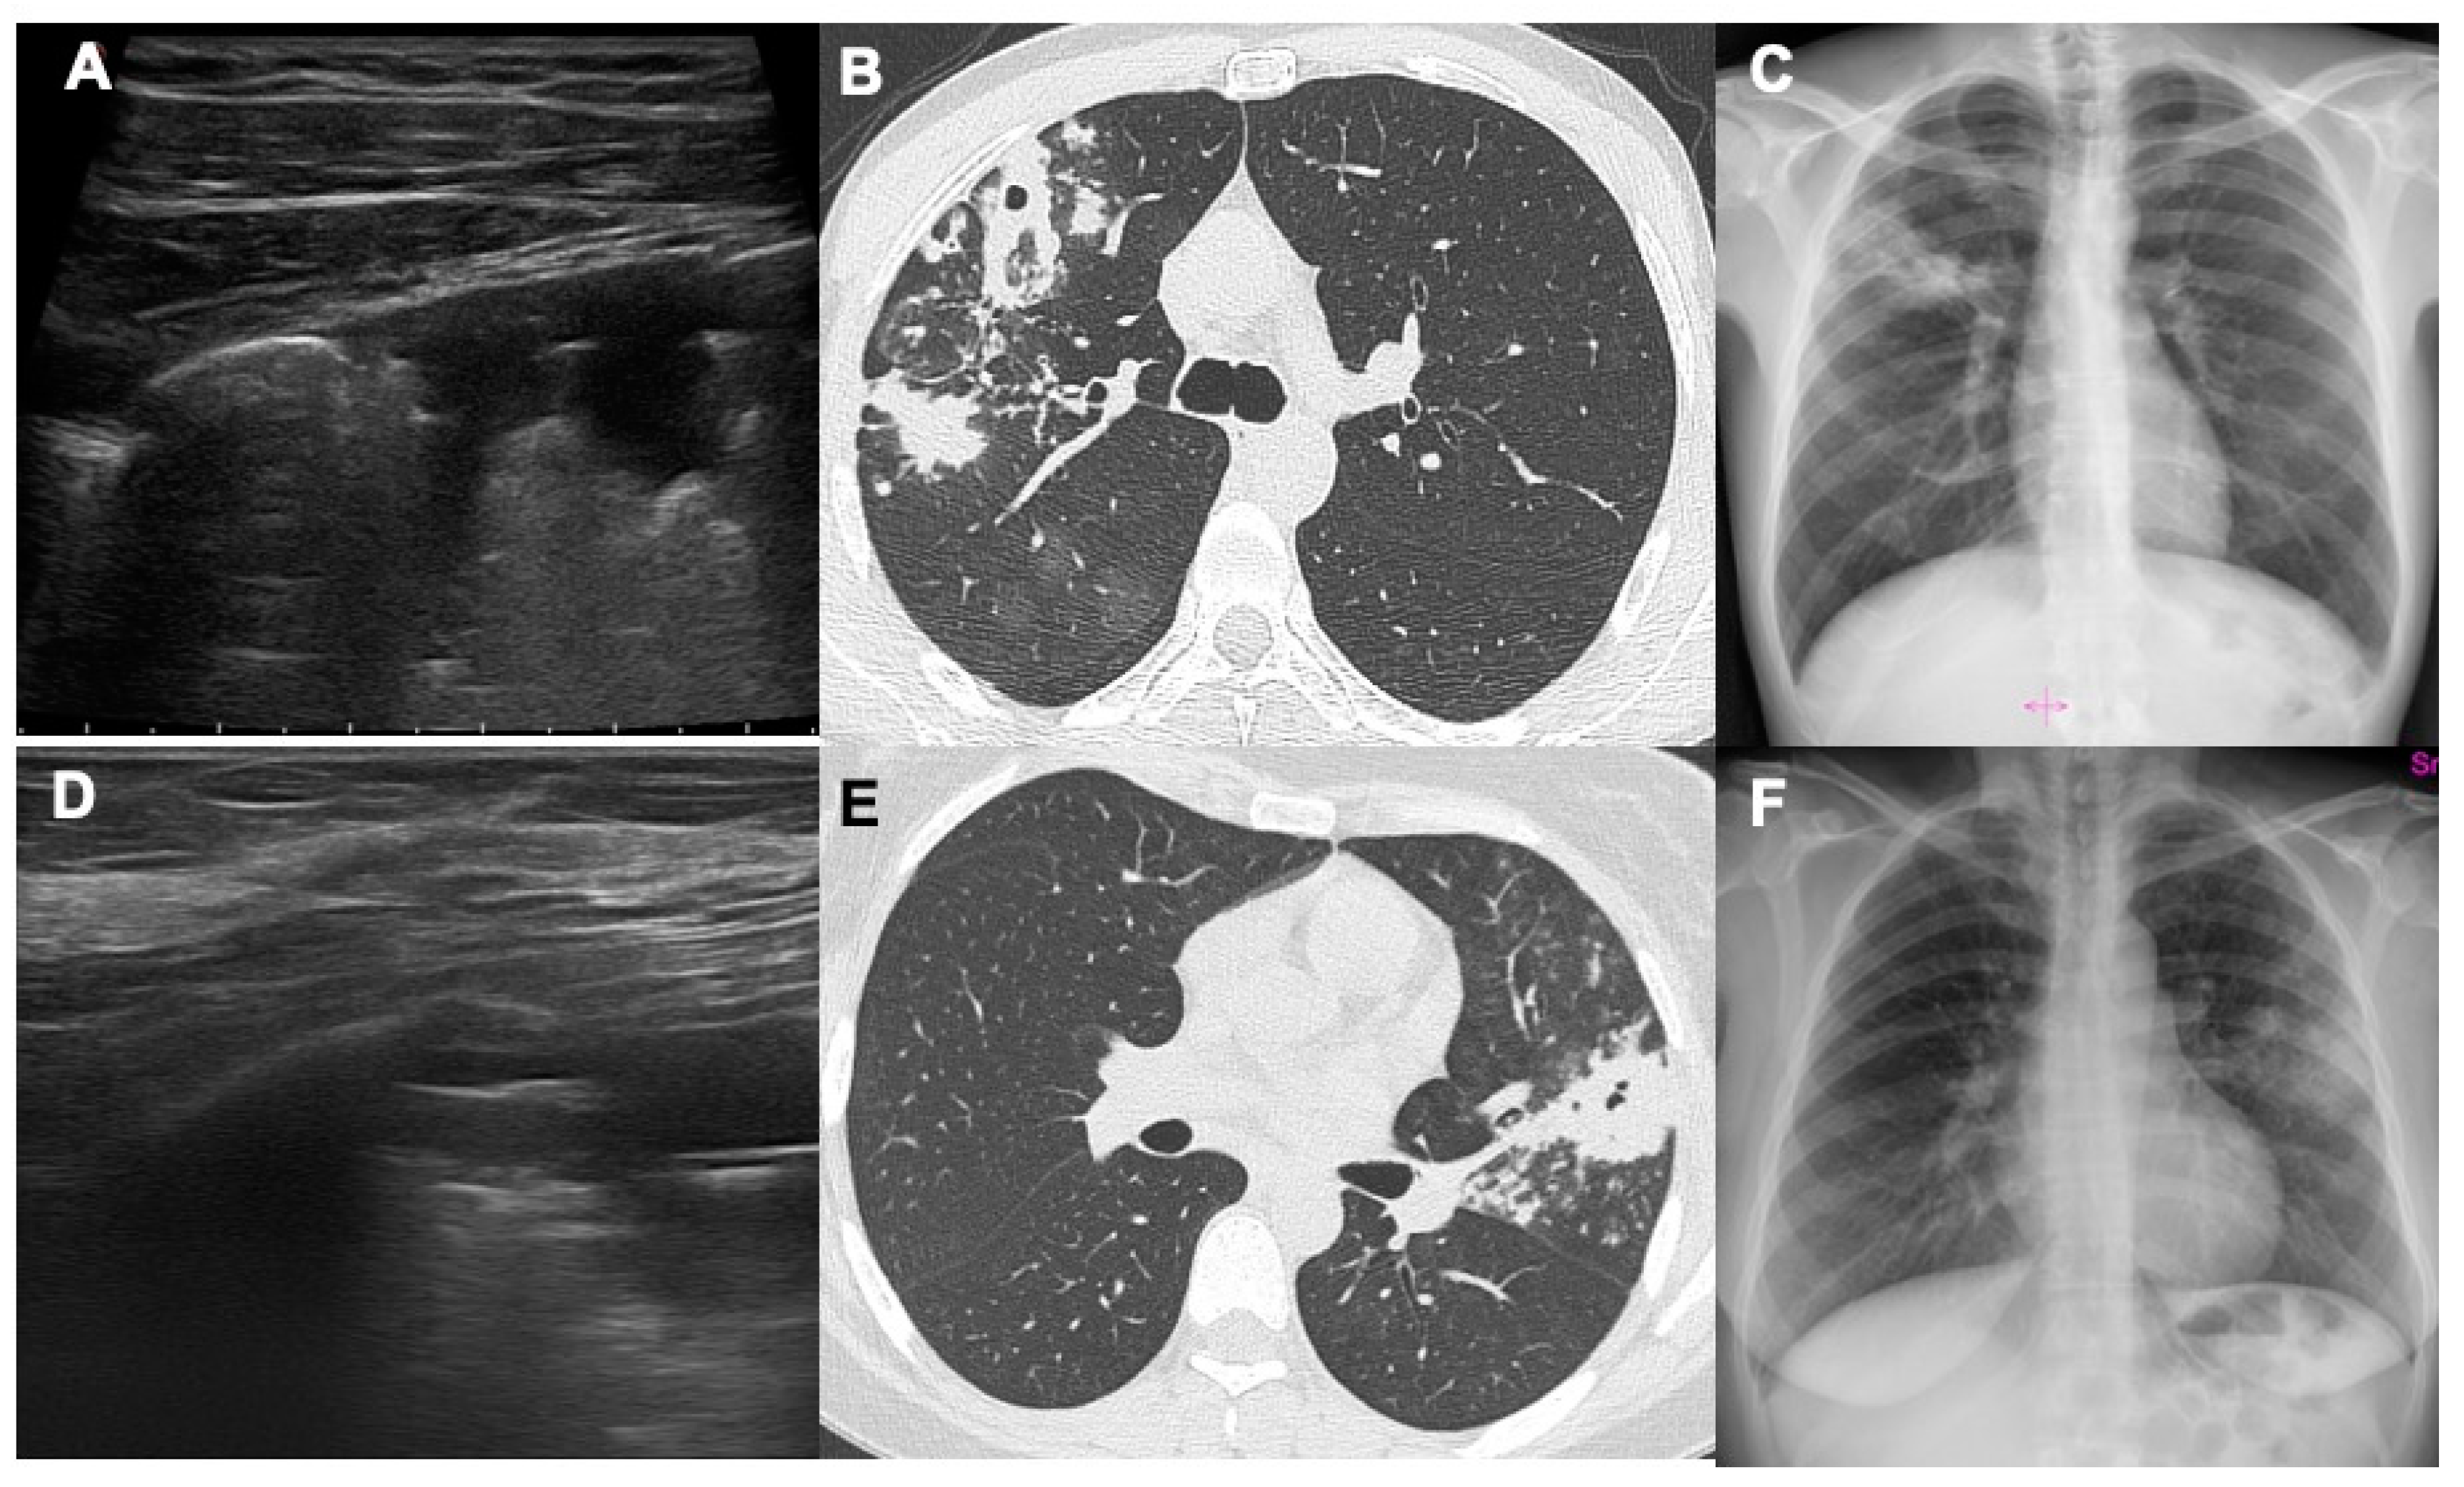

- Giannelli F, Cozzi D, Cavigli E et al. Lung ultrasound (LUS) in pulmonary tuberculosis: correlation with chest CT and X-ray findings. J Ultrasound 2022, 25(3):625-634. [CrossRef]

- Montuori M, Casella F, Casazza G et al. Lung ultrasonography in pulmonary tuberculosis: a pilot study on diagnostic accuracy in a high-risk population. Eur J Intern Med 2019 66:29–34. [CrossRef]